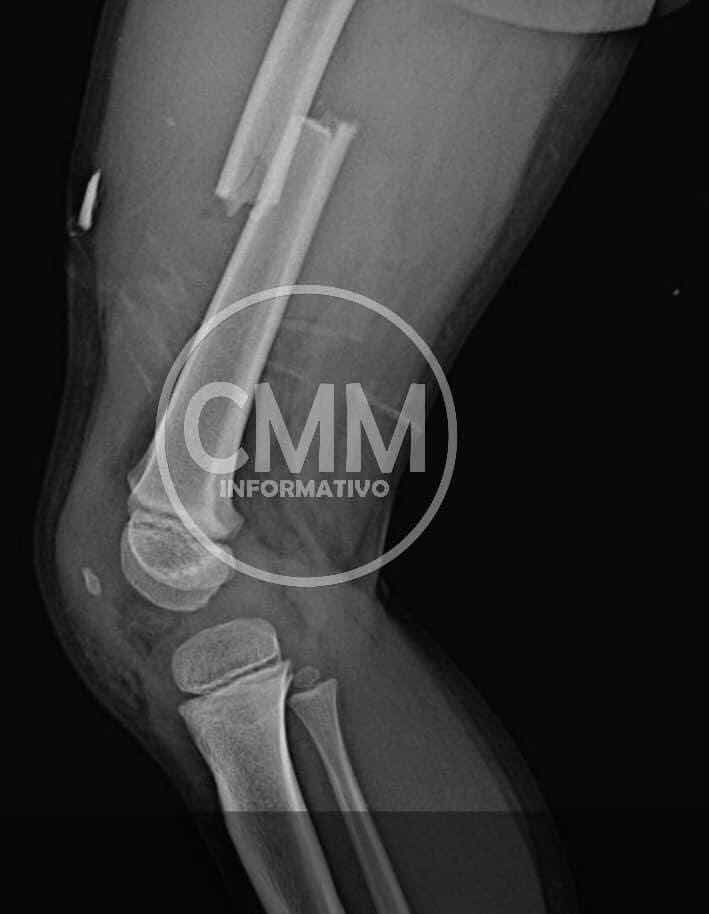

Mechoacan Oax., 27 enero 2022.El Niño Cristian David López Sanchez de 4 años de edad, tuvo un accidente y sufrió fractura de brazo 💪🏽 y pierna 🦵 por lo que, requiere apoyo económico para sus cirugías, es originario de Santa Catarina Mechoacan en la costa de Oaxaca.

El cual es un niño de tan solo 4 años de edad y tuvo un acidente el día 27 de enero del 2022, tuvo   una caída en el cual sufrió 2 fracturas,  una fue  en el  brazo izquierdo y la otra en la pierna derecha y, por lo cual,  el requiere dos operaciones, y los padres no cuentan con el dinero necesario,en estos momentos el niño está siendo trasladado en la ciudad de Oaxaca .....